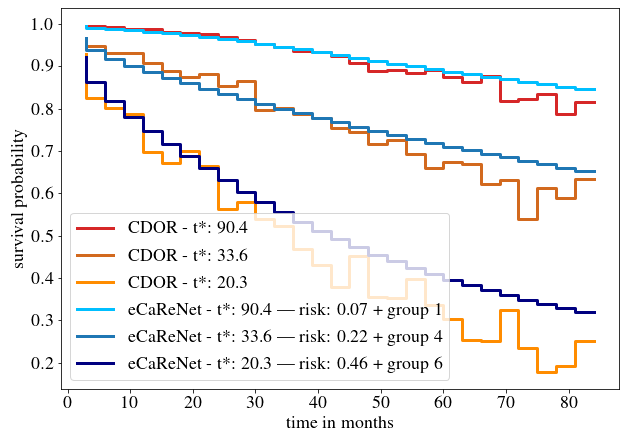

We start by comparing eCaReNet to two models proposed in the literature. First, we retrain our pretrained M (see \sectionrefsec:misup) with the Cox loss and output as proposed in DeepConvSurv by Zhu et al. (2016). To do so, the output needs to be reduced to only one node. That model reaches an AUC of 0.69 (c-index of 0.65) on the validation and 0.71 (0.64) on the test set. The test for d-calibration fails and also the Brier score of 0.305 (0.296 on the test set) indicates a non-calibrated model. As second comparison, we train M with the output structure and loss proposed in censoring-aware deep ordinal regression (CDOR) by Xiao et al. (2020). That model reaches an AUC of 0.77 on the validation and 0.78 on the test set and a c-index of 0.73 for both sets, but also fails in terms of calibration. Furthermore, the resulting survival curves are not monotonically decreasing, therefore biologically unreasonable (see \figurereffig:survcurves).

Compared to both previously described models, eCaReNet shows the best performance for all measures on the validation set (AUC 0.78, Brier score 0.107, c-index 0.75) and passes the chi-square test for d-calibration. On the test set it also obtains the best Brier score (0.109) and c-index (0.74) and passes the chi-square test for d-calibration. CDOR performs best on the test set’s AUC. In contrast to CDOR, eCaReNet outputs monotonically decreasing survival functions (see \figurereffig:survcurves).

In addition, we assign individual patients to 8 risk groups, to enable a relative ranking as detailed in \appendixrefapd:risk_strat. Risk groups further allow the evaluation of Kaplan-Meier curves (Kaplan and Meier, 1958) with a log-rank test, which is common in survival analysis (Li et al., 2015). Kaplan-Meier curves are calculated for the risk groups on the training, validation and test datasets. Overall, we can show that the risk groups stratify well on all sets. The results for the test set are shown in \figurereffig:risk_stratification, where five out of seven log-rank tests pass ().

Furthermore, we compare eCaReNet to annotations of an expert pathologist. In clinical practice, pathologists do not estimate relapse times for patients directly, but assign a Gleason score. We compare eCaReNet’s discrimination power to the assigned ISUP scores, since a higher ISUP score corresponds to an increased risk of relapse. eCaReNet reaches on par performance in terms of AUC and c-index with the pathologist’s annotations on the validation set (AUC 0.78 and c-index 0.75). Only on the test set, the ISUP annotation shows higher AUC and c-index. In contrast to our model that uses a single TMA spot image per patient, for the ISUP annotation the whole prostate tissue was available, giving Gleason-based survival prediction an advantage over model-based prediction.